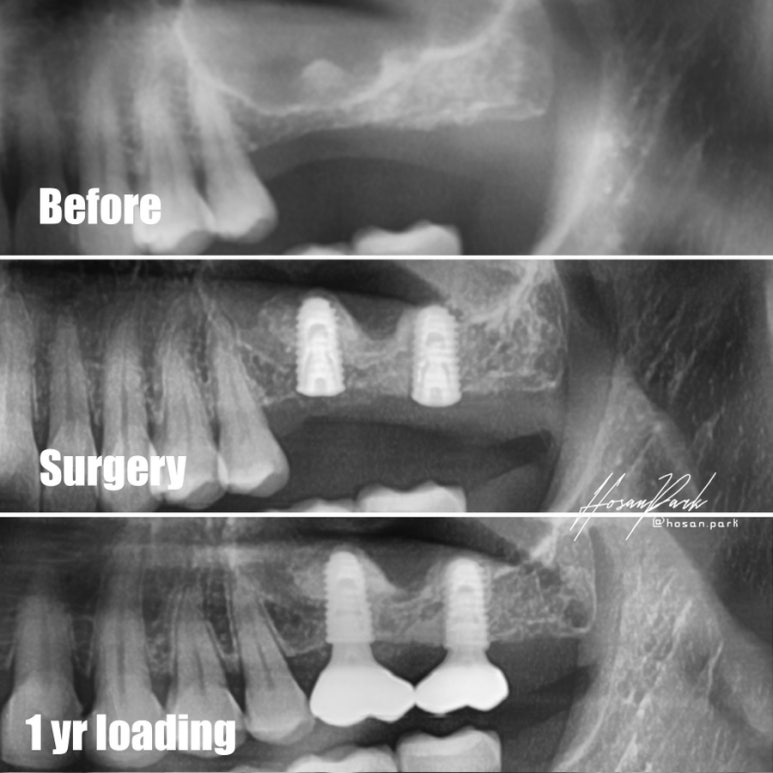

한번더 수술 과정 및 보철까지를 비교해 보았습니다.

위 환자분의 경우도 치아를 발치 후 상악동이 많이 확장되어 어금니쪽 임플란트를 심기 위해서는 상악동 거상술이 필요하신 경우 였답니다. 파노라마 엑스레이상 노란색으로 살짝 표시해 놓은 부분이 상악동과 치조골의 경계면이지요.

얼핏 봐서 대략 3-4mm 정도 밖에 잔존골이 남지 않아 많은 양의 상악동 뼈이식이 요구되는 상황이었답니다.

물론 통상적인 방법으로 상악동 거상술 먼저 시행 후 4-6개월을 기다렸다가 임플란트를 심는 방법도 고려해 볼 수 있었으나, 초기고정에 대한 확신이 있었기 때문에 동시 식립으로 계획하고 무사히 수술을 마치게 되었답니다.

수술 후 4개월 뒤에 보철물을 올렸고, 1년이상 무리없이 잘 사용하고 계시며, 뼈이식 재료들도 골화되어 엑스레이상 잘 유지되고 있는 모습을 보여주고 있답니다.